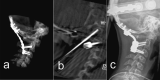

Methods: In this paper, we present a technical note on the use of 1:1 scale patient-specific 3D printed spinal models for preoperative assessment of feasibility of spinal instrumentation with conventional spinal implants in pediatric spinal pathologies.

Results: The printed 3D models fully matched the intraoperative anatomy and allowed a preoperative confirmation of the feasibility of the planned instrumentation with conventional screws for adult patients. In addition, the possibility of intraoperative model assessment resulted in better intraoperative sense of spinal anatomy and easier freehand screw insertion, thereby reducing the potential for iatrogenic injury. All 3D models were printed at the surgical department at a very low cost, and the direct communication between the surgeon and the dedicated specialist allowed for multiple models or special spinal segments to be printed for more detailed consideration.

Conclusions: Our technical note highlights the critical steps for preoperative virtual planning and in vitro testing of spinal instrumentation on patient-specific 3D printed models at 1:1 scale. The simple and affordable method helps to better visualize pediatric spinal anatomy and confirm the suitability of preplanned conventional spinal instrumentation, thereby reducing X-ray exposure and intraoperative complications in freehand screw insertion without navigation.